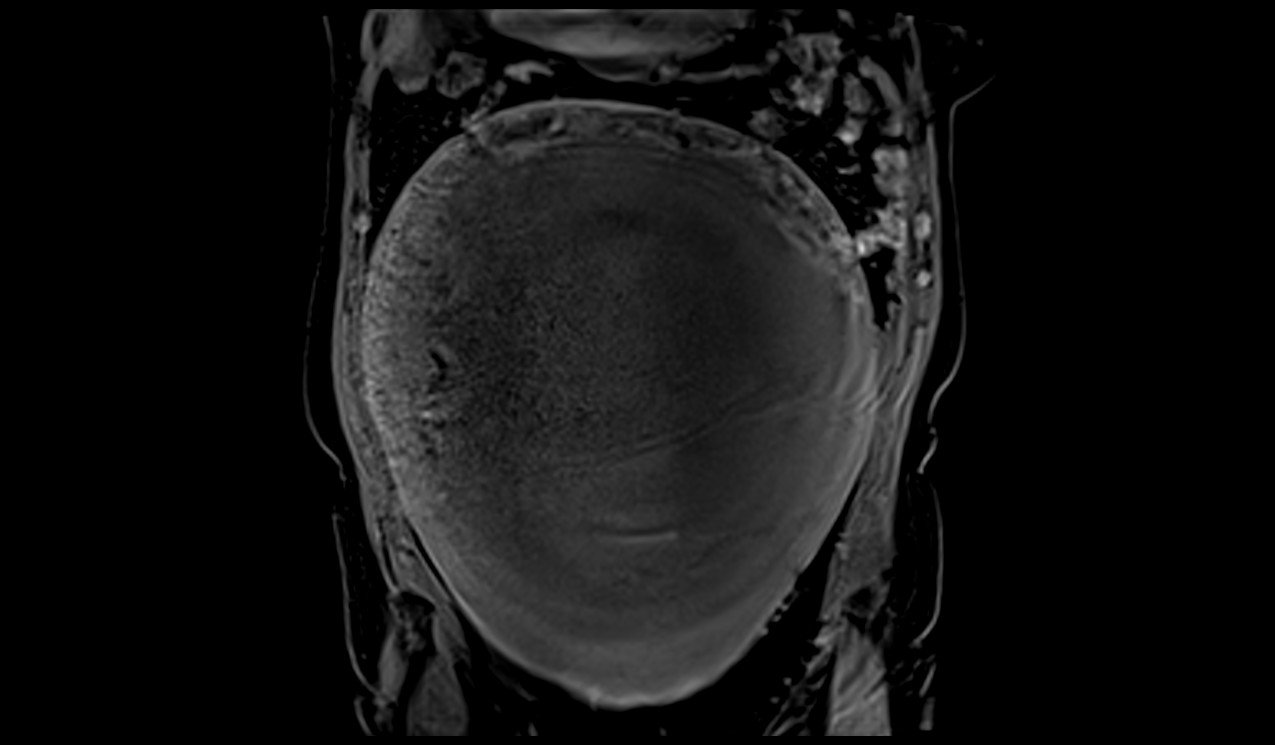

MRI Large abdomen and Pelvic Masses axial t1 dynaic image 3 - MRI